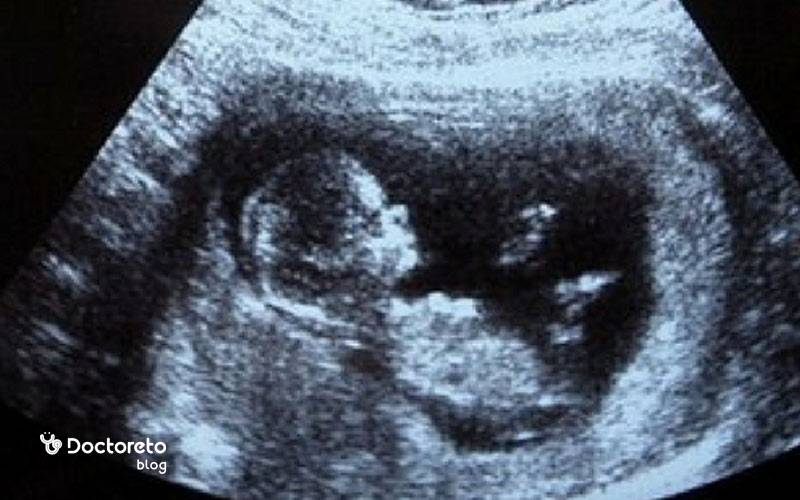

در جنین ۱۱ هفتهای، نسبت سر به بدن هنوز بزرگتر است اما گردن مشخصتر شده و بدن از حالت خمیده ابتدایی خارج میشود. انگشتها و انگشتان پا از هم جدا شدهاند، مفاصل زانو و آرنج فعالترند و جوانههای دندانی اولیه شکل گرفتهاند. کبد هنوز نقش پررنگی در خونسازی دارد و رودهها که تا همین حوالی در بند ناف بودند، بهتدریج به داخل شکم برمیگردند. شکل جنین در هفته یازدهم بارداری در سونوگرافی با ستون فقرات روشن و حرکات جهشی کوتاه قابلمشاهده است.

از نظر عملکرد، مسیرهای عصبی و مخچه رشد میکنند و همین باعث افزایش حرکات بازتابی میشود. بااینحال شما هنوز این حرکات را حس نمیکنید. پوست جنین نازک و نیمهشفاف است و عروق زیر آن دیده میشوند. استخوانسازی جنین 11 هفته آغاز شده و استخوانهای بلند پا و ساعد در تصاویر سونو نمایانترند. همه این تغییرات جنین ۱۱ هفته ای زمینه جهش رشدی سهماهه دوم را فراهم میکند. مهمترین تغییرات جنین در هفته یازدهم حاملگی عبارتند از:

در هفته یازدهم بارداری، سونوگرافی نقش مهمی در تأیید سلامت جنین و محاسبه دقیق سن بارداری دارد. اندازهگیری طول سری تا نشیمن (CRL) و بررسی شفافیت نوک گردن (NT) در این سونوگرافی برای ارزیابی اختلالات کروموزومی ضروری است. سونوگرافی در این هفته نشاندهندهٔ شکلگیری بیشتر اعضای بدن جنین است: صورت و اندامها واضحتر میشوند و حرکتهای ظریف در سونوگرافی مشاهده میشود. در این مرحله، جنین در سونوگرافی حدود ۴–۵ سانتیمتر طول دارد و ضربان قلب آن به وضوح شنیده میشود.

همچنین بهترین زمان برای سونوگرافی nt تی در هفته ۱۱ بارداری تا ۱۳ هفته و ۶ روز است. درصورتیکه تصویر سونوگرافی واضح نباشد، ممکن است پزشک از شما بخواهد که وضعیت خود را تغییر دهید یا سونوگرافی را دوباره انجام دهید. در سونوگرافی میتوان حرکات جنین را بررسی کرد. اگر دوقلو باردار باشید، در این مرحله سونوگرافی، بندناف جنینها و یک یا دو جفت را نشان میدهد. در سونوگرافی میتوانید ضربان قلب جنین را بشنوید.